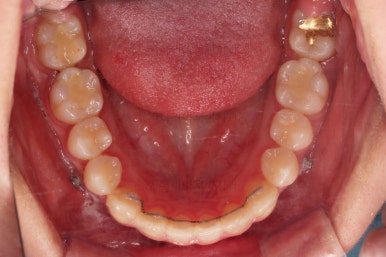

쓰러져 있던 치아도 장치를 부착하여 일으켜 세워주는 힘을 줍니다.

자칫 나머지 치열이 틀어질 수 있기 때문에 아랫니에는 부산교정 미니스크류를 이용해서 반작용을 막아줍니다.

점점 뒤쪽 치아가 바로 일으켜세워지고 있네요.

생각보다 많이 썩은 상태였어요.

앞쪽 치아 하방으로 갇혀 있으면서 훨씬 심각한 상태까지 충치가 진행되었던거죠.

기타 부위들의 디테일을 좀 더 맞춰주고 부산교정 치료를 종료합니다.

전후사진을 비교해 볼게요.

약간의 주걱턱, 돌출입은 고칠 의사가 없어서 그대로 유지하였고 주걱턱 패턴으로 인한 부정교합 부분을 개선했으며 무엇보다 중요한 것은 쓰러져서 많이 썩어있던 치아를 자칫 치료 못할 뻔 했는데 교정치료와 병행하여 훌륭하게 치료를 하여 살려 썼다는 점입니다.